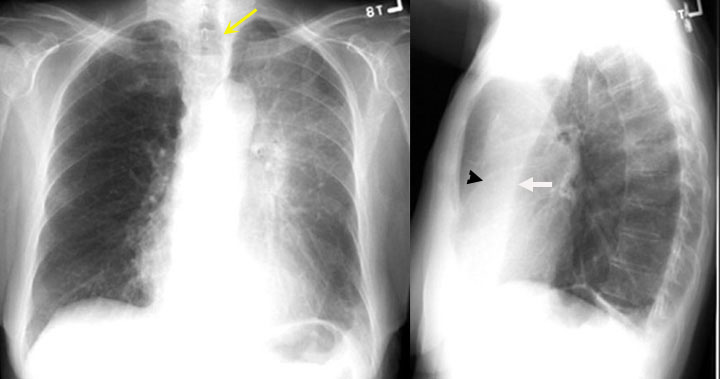

Resorptive Atelectasis of LUL

Cancer Lung

LUL atelectasis due to endobronchial obstruction. Once the bronchus is obstructed, there is no ventilation and the air gets absorbed. The distal lung is now devoid of air and becomes atelectatic.

Black arrowhead pointing to atelectatic LUL.

Signs of loss of lung volume:

Trachea (yellow arrow) is shifted to left.

White arrow is pointing to the bowing left oblique fissure. The fissure has moved forwards due to loss of LUL lung volume.